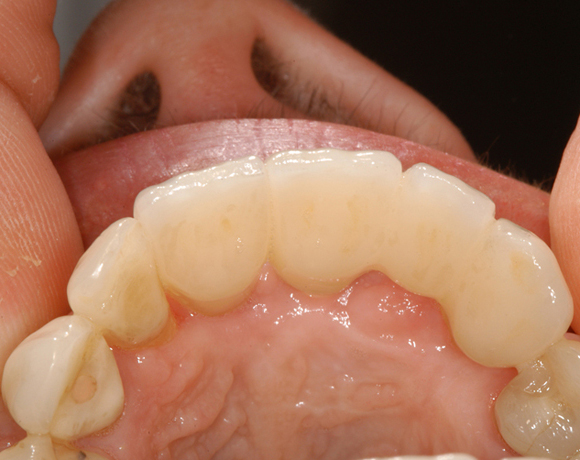

Das vollkeramische zweiteilige Implantat hat durch seine weiße Farbe im Frontzahnbereich keine ästhetischen Nachteile.

Im vorliegenden Patientenfall mussten die 11 bis 22 aus parodontalen Gründen extrahiert werden. Die Zähne hatten Lockerungsgrad III, und es bestand ein starker horizontaler Knochenabbau. Das Ergebnis zeigt die Abschlusssituation nach Knochenaufbau und der Insertion von drei Vollkeramikimplantaten.